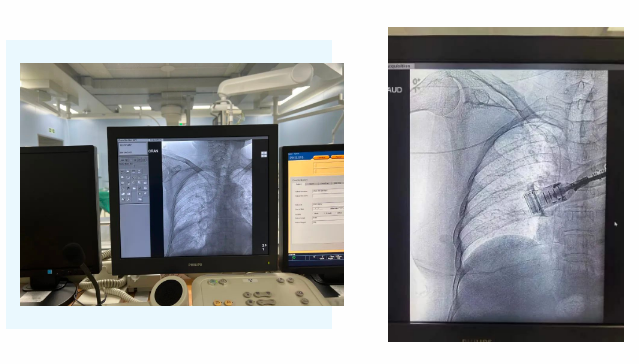

在麻醉手術(shù)中心的配合下,手術(shù)首先由韓海靜護士長在超聲引導(dǎo)下應(yīng)用“塞丁格”法穿刺將針尖一樣細的導(dǎo)絲送入血管,術(shù)中在DSA透視下將導(dǎo)管沿著血管送達上腔靜脈,尖端精準(zhǔn)定位至上腔靜脈開口處。隨后,胸腔外科支亞男主治醫(yī)師在穿刺點下方取2厘米小切口內(nèi)進行上臂港囊袋和隧道的制作及導(dǎo)管與港座連接,最后進行港體埋植及皮內(nèi)縫合,使患者切口隱蔽美觀創(chuàng)傷小,術(shù)中出血量極少。手術(shù)在X片影像留影,最終手術(shù)順利完成。